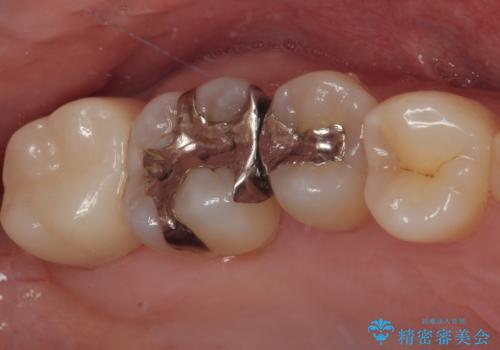

銀歯をセラミックにしたい オールセラミッククラウン

担当医 有澤哲郎